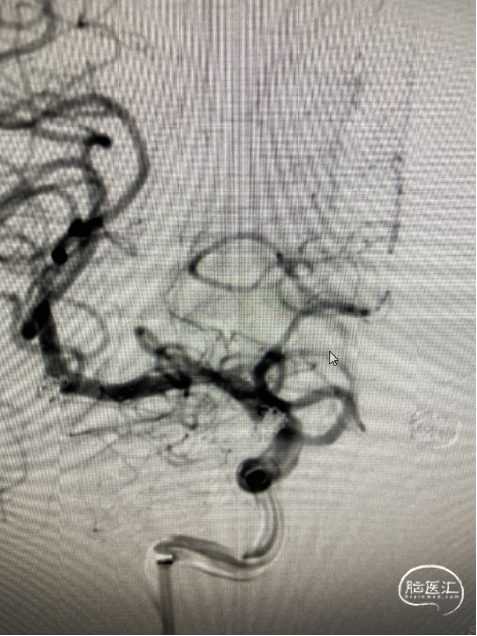

术 后

![]()

替罗非班6ml/h持续泵入24小时后桥接双抗.

2022-2-12头颅CT复查:左侧基底节区腔隙灶、脑白质变性、脑萎缩、左额叶斑点状高密度影无著变,鞍区术后改变。